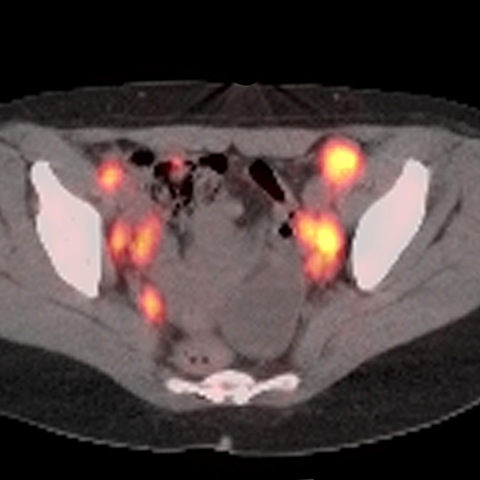

40 year old male presents with lymphadenopathy and unexpected weight loss [4 of 4]